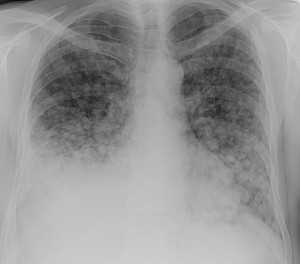

Слева - рак почки с метастазами в легкие, прогноз в данном случае неблагоприятный ввиду метастатического плеврита и дыхательной недостаточности. Определяются очаги с обеих сторон. Справа - мелко- и среднеочаговая диссеминация при раке печени.

Множественные гематогенные вторичные узлы при раке почки, компьютерная томография (КТ).

Лимфогенные метастазы на рентгене и КТ выглядят как множественные мелкие очаги с диссеминированным распространением, локализованные в междольковых перегородках, в плевральных листках. Вокруг можно видеть характерную картину ракового лимфангиита. Кроме того, практически всегда выявляются патологически измененные и увеличенные лимфатические узлы средостения. Лимфогенное метастазирование необходимо дифференцировать с милиарным туберкулезом, саркоидозом. Иногда это требует привлечения Второго мнения.